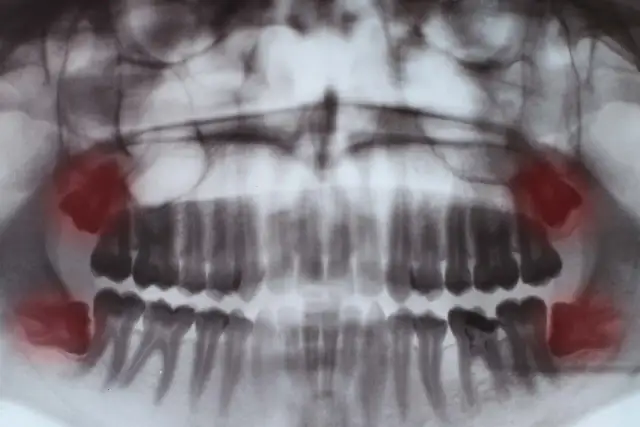

Ile trwa usuwanie szóstki? Dowiedz się o czasie zabiegu, bólu, gojeniu i zaleceniach po ekstrakcji zęba trzonowego. Sprawdź nasz poradnik!